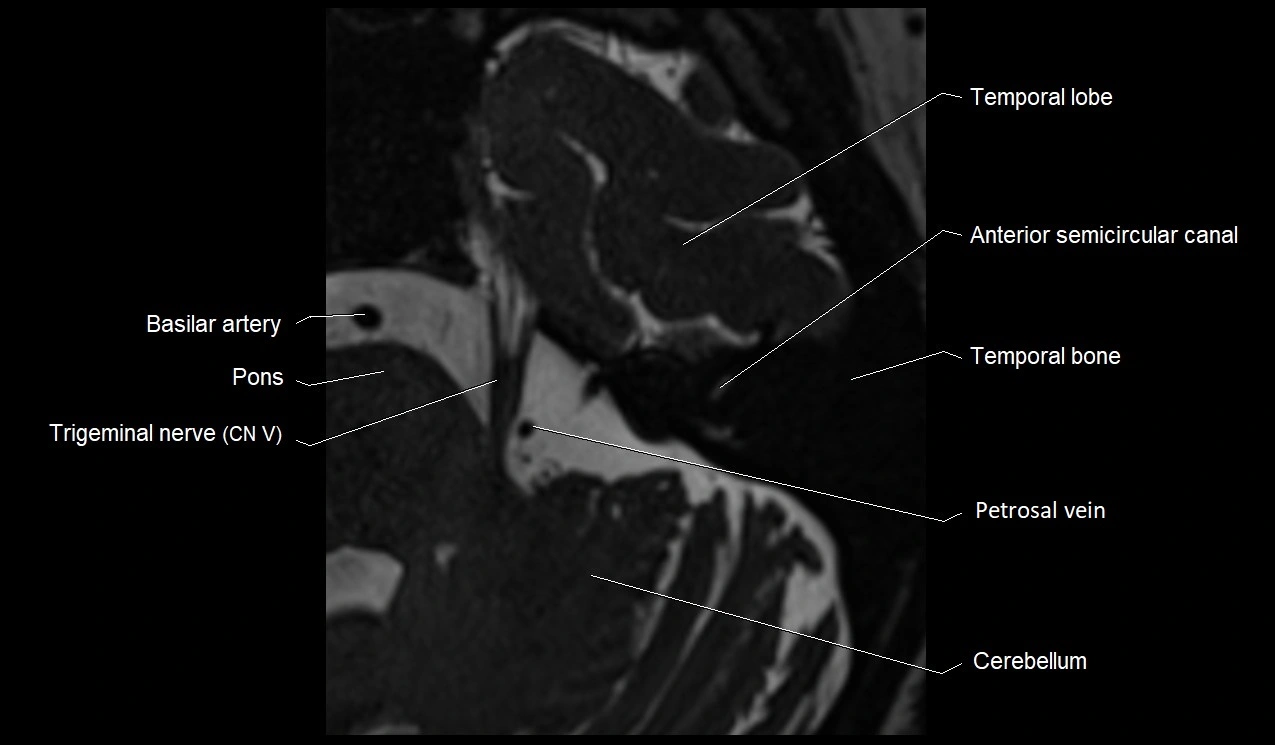

MRI images

image